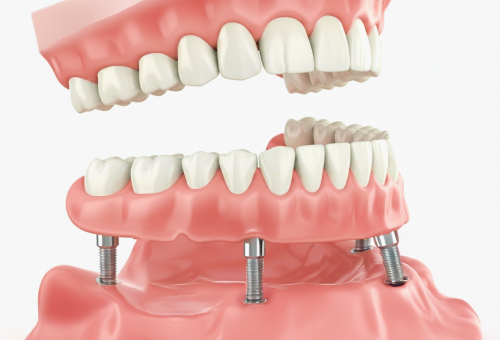

3

임플란트틀니

소수의 임플란트를 식립하여 틀니의 고정성을 높이고, 기존 완전틀니의 유지력과 안정성을 향상시킵니다.